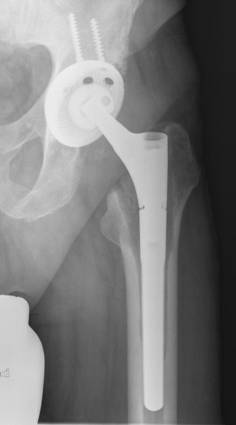

In most two-stage revisions an antibiotic-containing spacer is usually placed in position for a certain period of time before the final prosthesis is implanted [17,20,30,33,34]. The function of the spacer is on the one hand to release the antibiotic into the infected bed of the prosthesis and on the other to minimize soft-tissue contractures, retain soft tissue tension and so maintain reasonable functionality until a prosthesis can be re-implanted [30]. There are several different types of spacer: monoblock and two-part spacers, commercially available and customized spacers made in the operating theatre. The potential disadvantages of the monoblock spacers are spacer fracture and bone resorption while the two-part spacer can produce abraded cement particles [35-37]. In order to avoid spacer fractures we use a two-part spacer where the cup-shaped acetabulum spacer is formed out of antibiotic loaded cement (with a specific mixture of antibiotics recommended by the microbiologist). The spacer stem component consists of old prosthesis stem models, monoblock devices in most cases and no longer used for primary implantations, that are encased in antibiotic-supplemented cement and, just before implantation, coated in the patient's own blood in order to facilitate easier removal. The two spacer components are connected by a metal headpiece (Figure 1) [20]. However, a recent analysis of synovial membranes obtained during the operation to remove the spacer and to implant the new prosthesis revealed the presence of abraded cement debris, in particular, zirconium dioxide particles [unpublished data].

Figure 1

Radiograph of a hip spacer of a 63year old man with late periprosthetic infection of the left hip